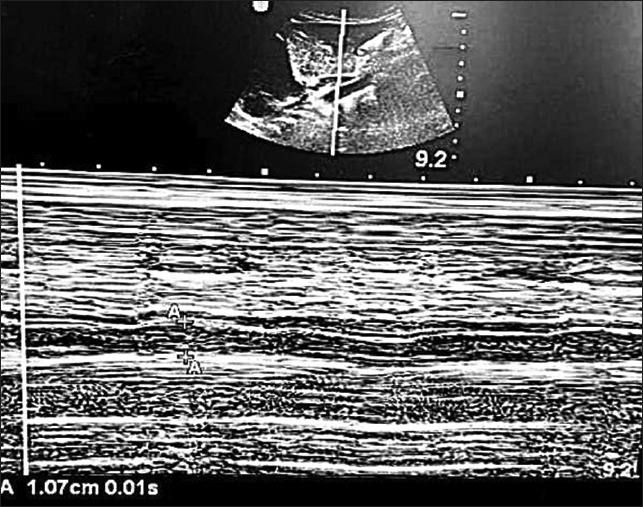

Material and methods: A single-center prospective observational study was conducted involving pediatric patients aged 1-12 years undergoing elective surgery. Ethical approval and written consent were obtained, with exclusions for major cardiovascular issues. Ultrasound measurements of IVC and aorta were performed by two observers during spontaneous and controlled ventilation in the subxiphoid transabdominal long-axis view. Reliability was assessed through statistical analyses, including the intraclass correlation coefficient and Bland-Altman analysis.

Results: Mean values of IVC and aorta diameters were summarized for both observers during different ventilation modes. The intraclass correlation coefficient indicated excellent to good agreement between the observers for both spontaneous and controlled ventilation scenarios. Bland-Altman analysis revealed no fixed or proportional errors, confirming the reliability of the measurements.